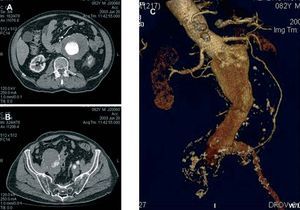

Contrast-enhanced computed tomography (CT angiography) provides high-resolution images and the possibility of 3-dimensional reconstruction. It is the technique of choice in the diagnosis and the preoperative study. The aortoiliac anatomy, the characteristics of the wall (inflammation, calcification, signs of rupture, thrombus), the visceral vessels and anatomical variations (horseshoe kidney, left renal vein, or left IVC) can be evaluated in detail (Figure 1). The disadvantages are the radiation and the use of a contrast agent. Contrast-enhanced magnetic resonance (MR) has the same properties as CT angiography, but eliminates the risk of nephrotoxicity and ionizing radiations (Figure 2). The degree of stenosis in visceral vessels may be overestimated, it does not detect calcifications and it produces artifacts in individuals with steel implants. However, in the follow-up of endoprostheses made of nitinol, MR angiography has been found to be useful in the detection of leaks.31-33

Figure 1. Axial images of abdominal aortic aneurysm and both iliac arteries (A and B). Detailed 3-dimensional reconstruction of the anatomy.